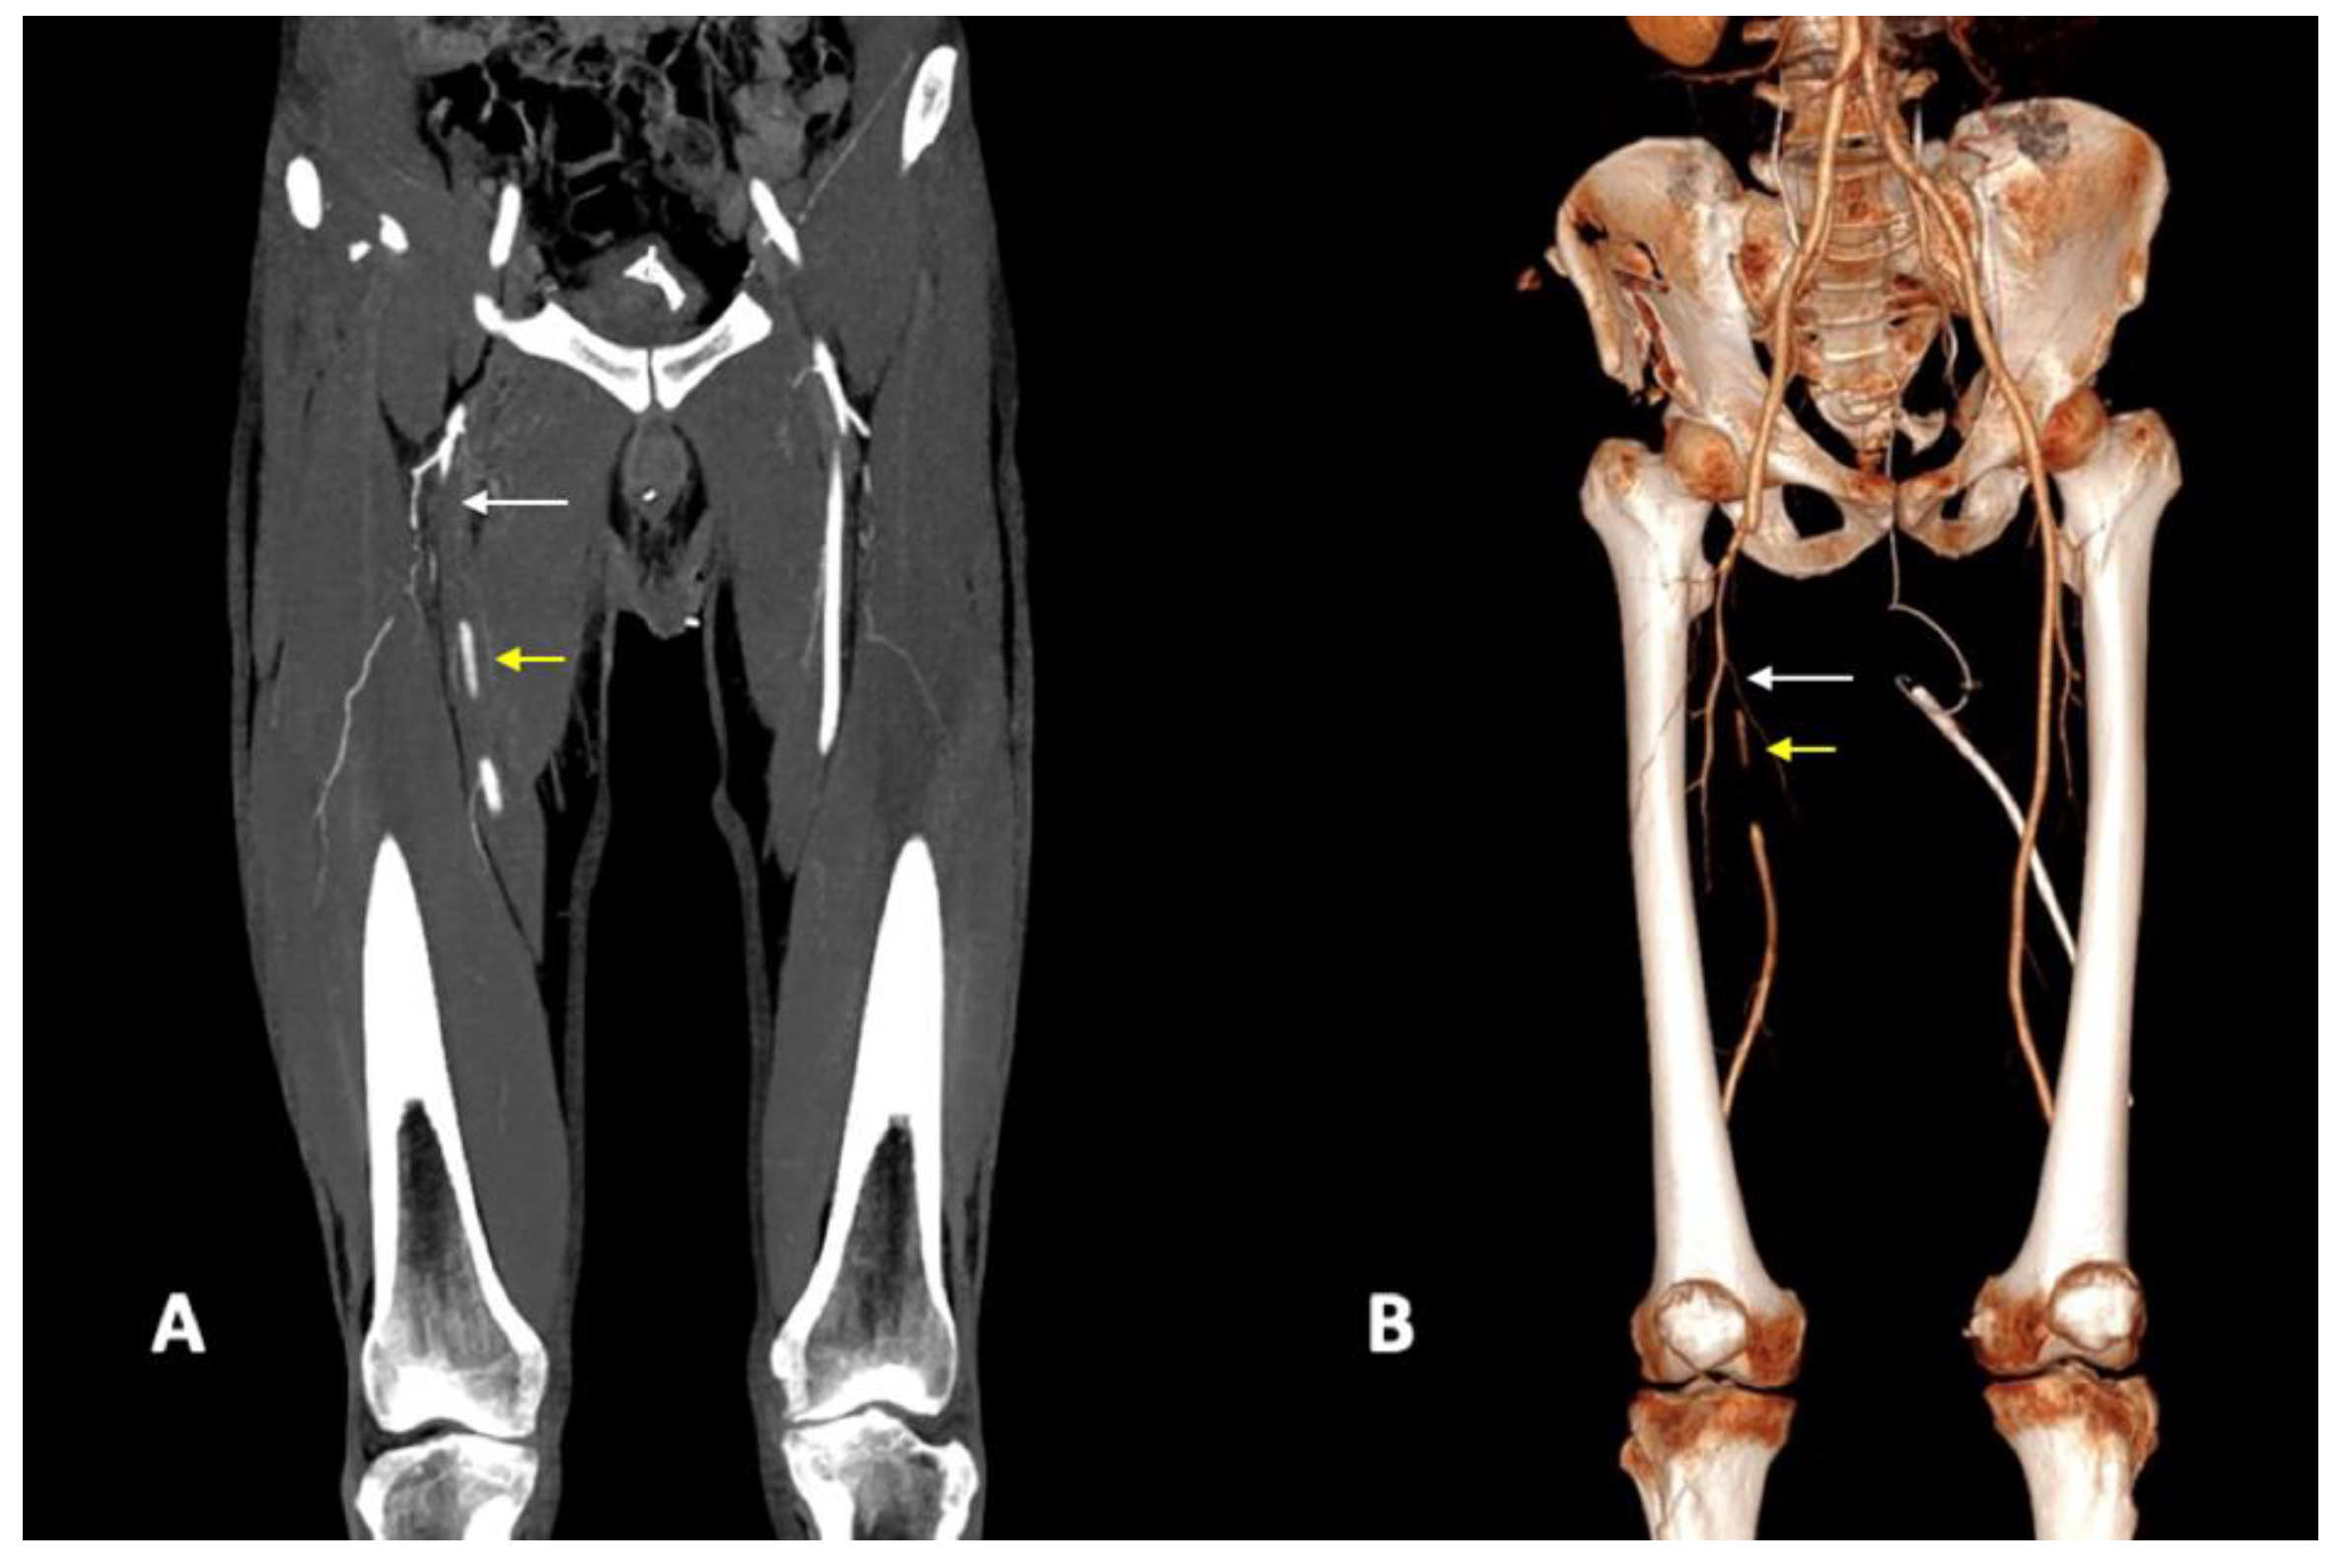

3.2. CTA Imaging Findings